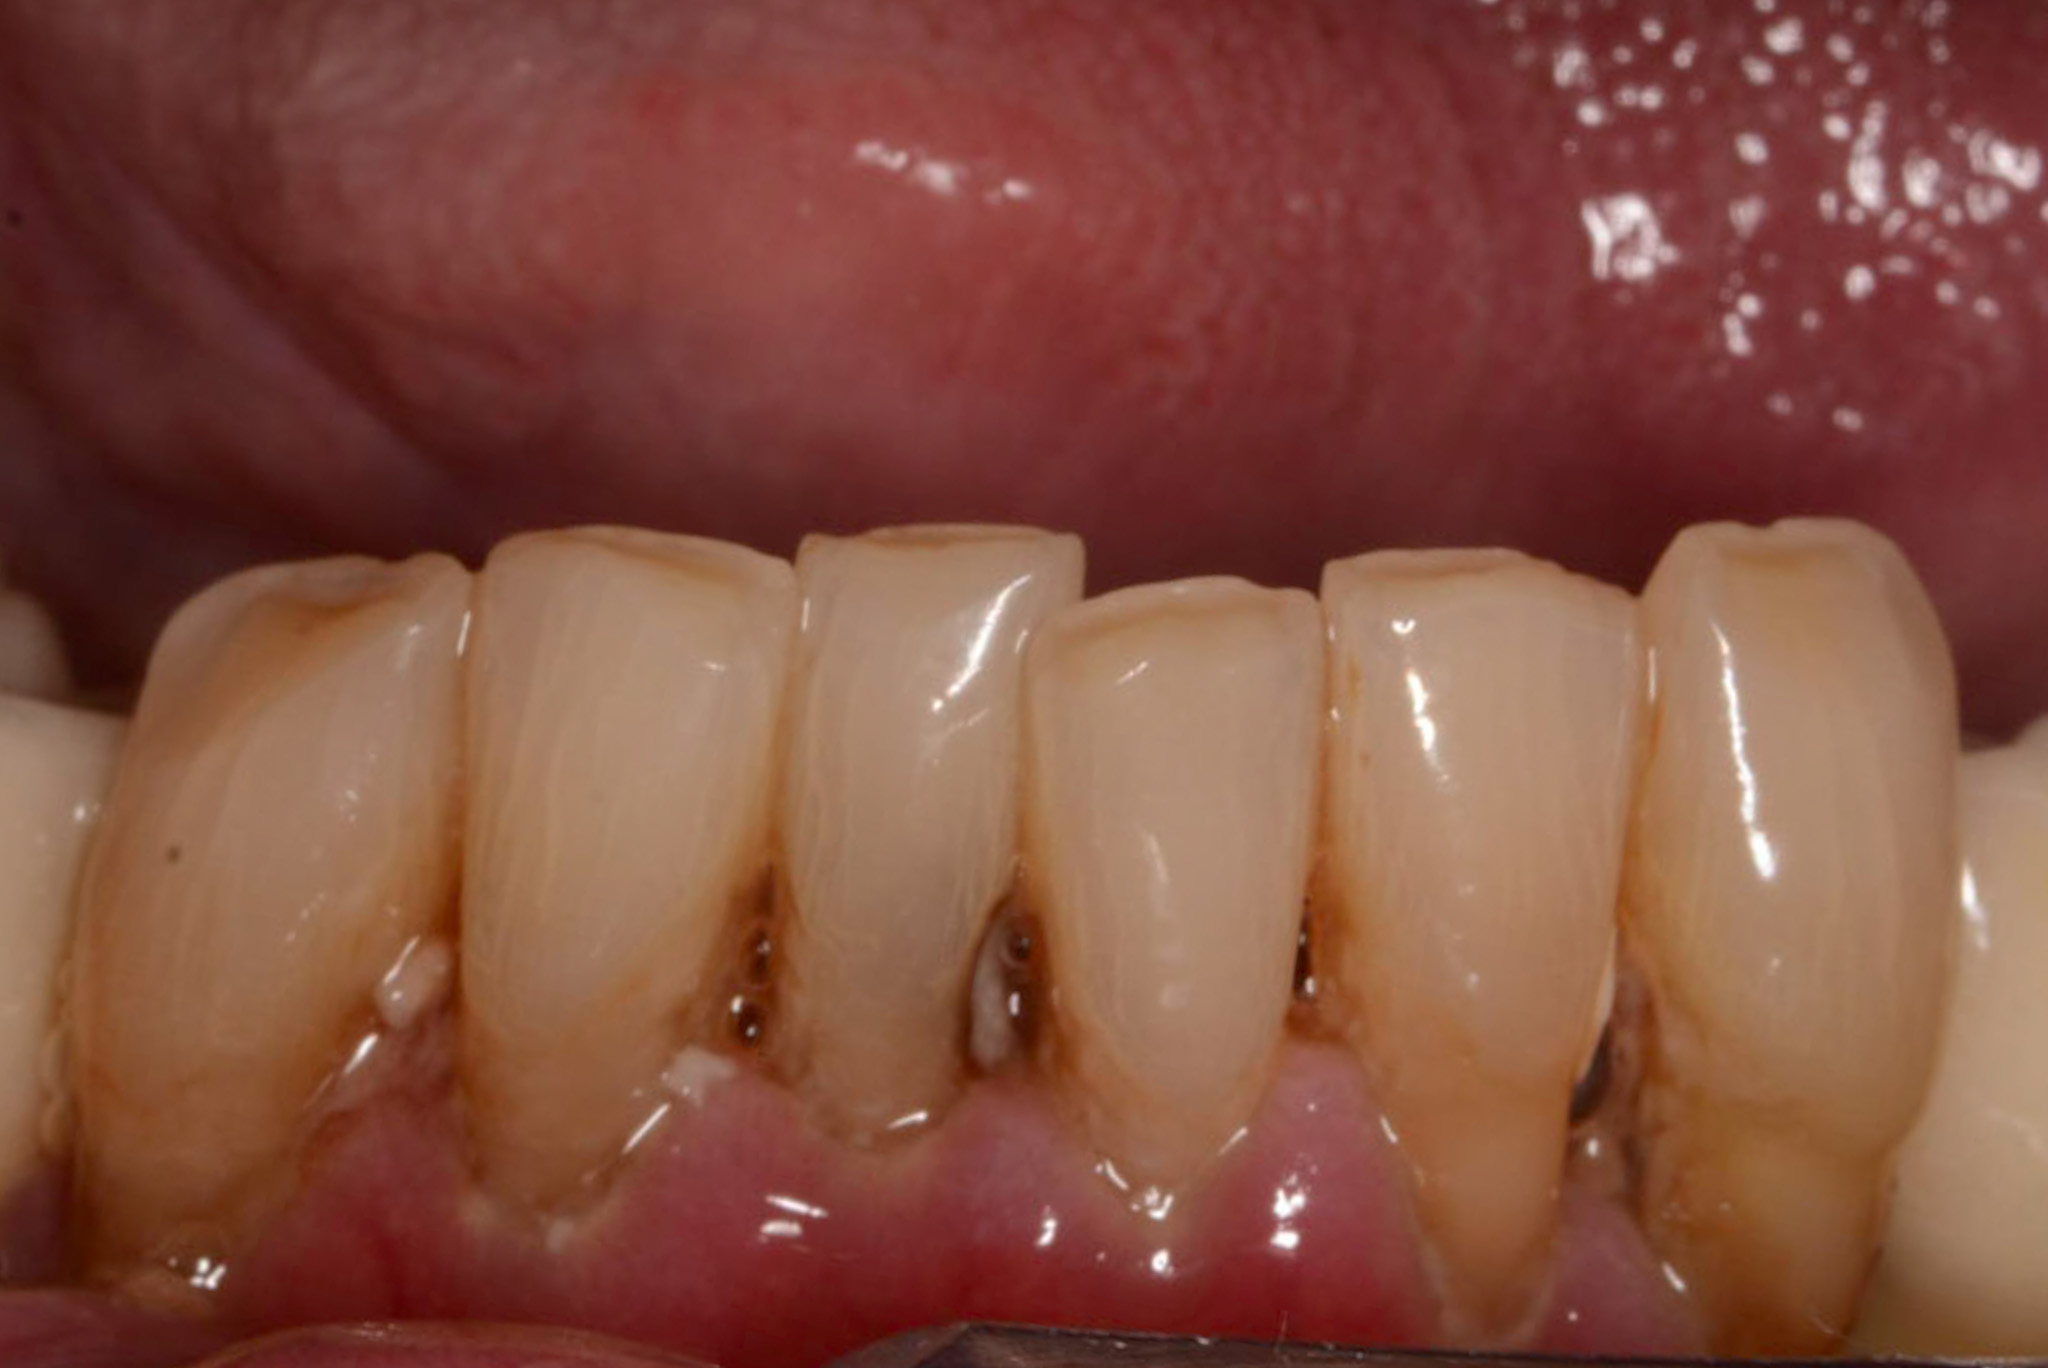

Klinisch ist eine atrophische Schleimhaut zu erkennen, diese ist sehr schmerzhaft für den Patienten. Weitere Symptome:

Ein erhöhtes Risiko für orale Mukositis besteht bei schlechter Mund- und Prothesenhygiene sowie bei Xerostomie. In der Anamnese können Risikofaktoren für eine bestehende medikamenteninduzierte Hyposalivation bereits erfasst und beim intraoralen Befund kann eine Mundtrockenheit erkannt werden (geringe Speichelfließrate, Spiegel bleibt an Mundschleimhaut kleben).

Es empfiehlt sich vor Beginn der onkologischen Therapie, eine PMPR durchzuführen. In diesem Zusammenhang kann auch ein Plaquebefund mittels Plaquerevelatoren erhoben werden, um den Patienten individuell zu instruieren, ebenso motiviert er für eine effiziente häusliche Mundhygiene. Empfehlungen für die häusliche Mundhygiene bei Mukositis: